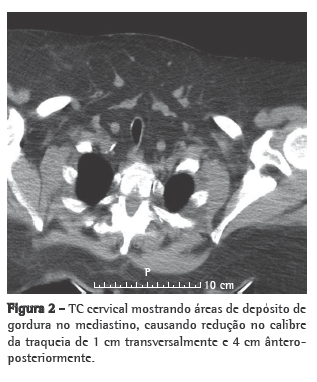

As condições clínicas do paciente melhoraram progressivamente, com a subsequente redução das pressões BiPAP e do uso do ventilador, que foi interrompido no 6º dia de internação em virtude do aparecimento de ulcerações faciais causadas pela máscara nasal. Durante a primeira noite sem ventilação não-invasiva, houve longos períodos de dessaturação de oxigênio (SpO2 < 88%) e ronco. O paciente foi então submetido à TC cervicofacial (Figuras 1 e 2) e a um estudo cardiorrespiratório do sono.

O estudo do sono levou aproximadamente 8 h, revelando grave apneia obstrutiva do sono (índice de apneia-hipopneia: 37 eventos/h; índice de apneias obstrutivas: 29 eventos/h; mediana de saturação periférica de oxigênio durante o sono: 88%; índice de dessaturação de oxigênio: 51%/h; e SpO2 mínima: 51%). A TC revelou várias áreas de depósitos de gordura no mediastino, causando uma redução no calibre da traqueia de 1 cm transversalmente e 4 cm ântero-posteriormente. A titulação da continuous positive airway pressure (CPAP, pressão positiva contínua nas vias aéreas) foi realizada na segunda noite, e o paciente recebeu alta. Em casa, o paciente permaneceu em ventilação BiPAP (EPAP: 8 cmH2O; IPAP: 16 cmH2O), realizada através de almofadas nasais (Figura 3).